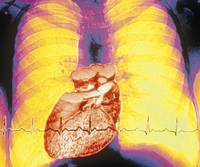

Dronedaron: ABD Gıda ve İlaç Dairesi (FDA) dronedaron ve bu maddenin kardiyovasküler vaka riskinde yol açtığı artışa ilişkin bir güvenlik bildirimi yayınladı. Bildirimde standart tedavinin en üst seviyesinde dronedaron kullanılarak yapılan kalıcı atriyal fibrilasyon sonucu çalışmasını (PALLAS) yeniden ele alarak varılan sonuçlara yer verildi.

Vareniklin: FDA 16 Haziran’da yaptığı duyuruda kalp damar rahatsızlığı olan hastalarda vareniklin kullanımının bu hastaların kardiyovasküler vaka yaşama riskini az da olsa arttırdığını belirtti. Buna göre vareniklin içeren Chantix adlı sigarayı bırakmaya yardımcı ilacın “Uyarı ve Önlemler” bölümüne konuya ilişkin güvenlik bilgisi ekleneceğini duyurdu.